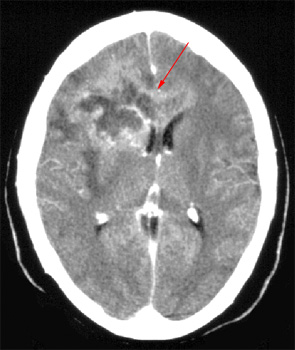

Head CT > Tumor > Glioblastoma Multiforme

Glioblastoma Multiforme is the most aggressive grade of astrocytoma. The two-year survival rate of patients diagnosed with Glioblastoma Multiforme is 10-15%. On CT, GBM is characterized by necrosis and irregular enhancement. It is one of very few lesions that frequently cross the corpus callosum.

![]() Notice the ill-defined low density in the right frontal region. An image post contrast

administration in the same patient reveals patchy |